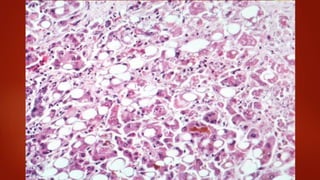

The morphology of chronic hepatitis is extremely variable.

When mild, a predominantly lymphocytic infiltrate may

occur just within the portal tracts. Frequently, steatosis is

observed along with lymph node-like aggregations within

the hepatic parenchyma

When severe, hepatocyte necrosis may be apparent.

Progression to cirrhosis is manifested by increasing fibrosis.

Morphology

Chronic Viral Hepatitis